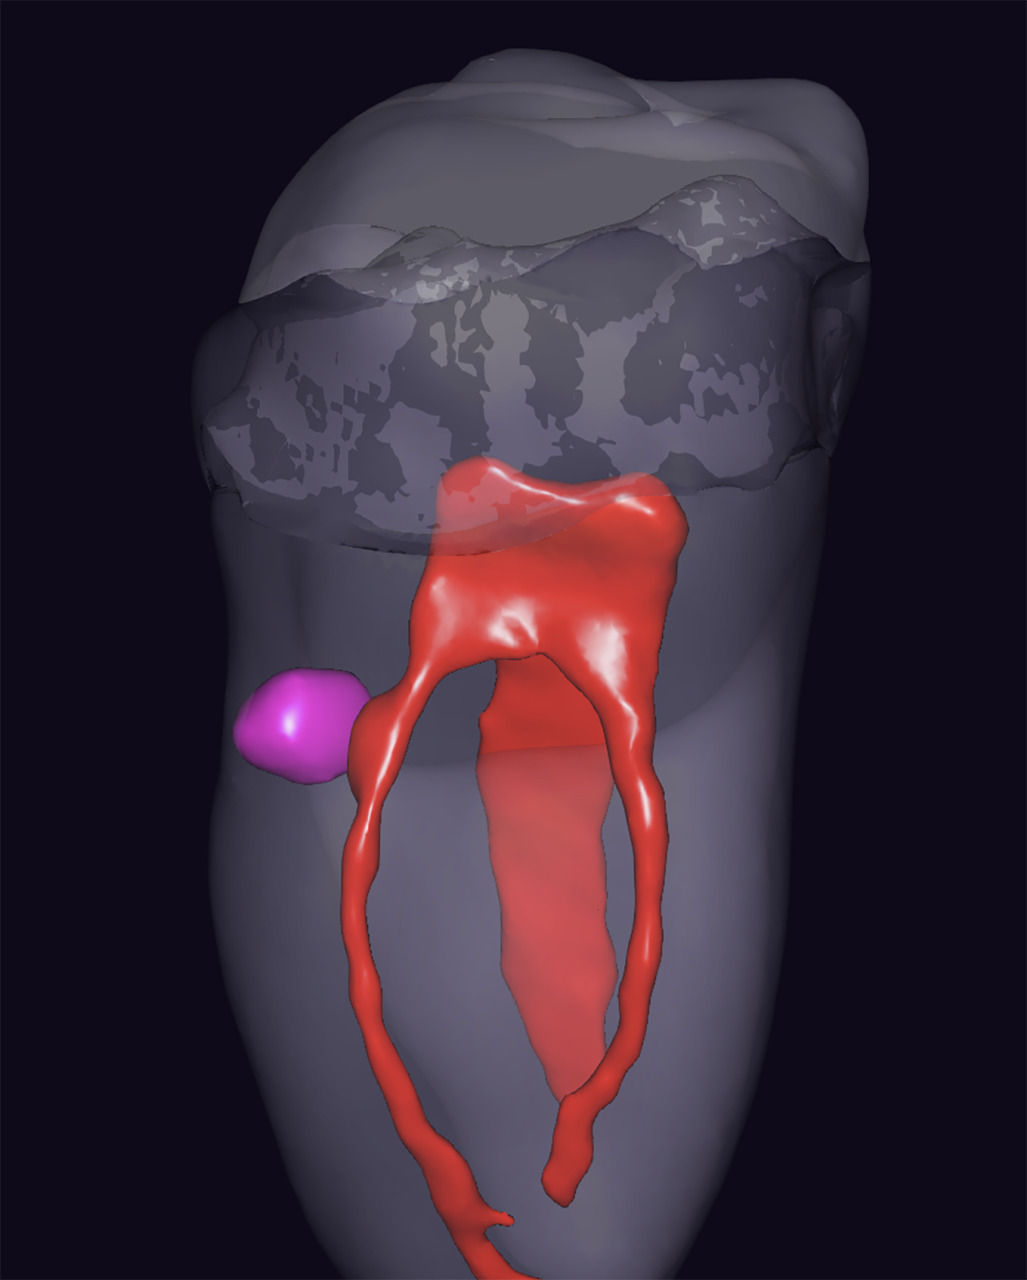

Pour décider de l’approche thérapeutique la moins invasive possible, un CBCT moyen champ a été réalisé. Sur cet examen, la lésion est clairement visible (Fig.2). L’analyse méthodique de différentes coupes permet de mettre également en évidence des lésions sur les dents 35 et 27. Néanmoins, ces lésions sont juxta-gingivales et ressemblent plutôt à des lésions d’usures. Sur la dent 36, la lésion présente des limites déchirées, et son rapport avec la pulpe n’est pas évident.

Afin d’avoir une meilleure lecture de la situation clinique, les fichiers DICOM sont intégrés dans un logiciel de lecture et de segmentation utilisant l’intelligence artificielle (www.diagnocat.eu).

Sur les différentes images obtenues par segmentation et reconstitution 3D (Fig.3 et 4), on voit clairement que :

– la lésion a des limites « déchirées », ce qui confirme le diagnostic de résorption externe,

– la lésion est en contact direct avec la pulpe radiculaire du canal MV de la racine mésiale de la dent (Fig.5a et 5b),

– la corne pulpaire est facilement repérable, et surtout, très facile à projeter sur la face occlusale.

Fig.3 : Reconstitution 3D – vue sous un autre angle.

Fig.4 : Reconstitution 3D centrée sur la lésion, vue frontale.

Fig.5a et 5b : Reconstitutions 3D montrant la communication entre la lésion de résorption et la pulpe radiculaire du canal MV.